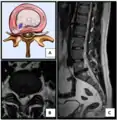

Herniated disc at C6–C7 level

Cervical disc herniations occur in the neck, most often between the fifth and sixth (C5–6) and the sixth and seventh (C6–7) cervical vertebral bodies. There is an increased susceptibility amongst older (60+) patients to herniations higher in the neck, especially at C3–4.[23] Symptoms of cervical herniations may be felt in the back of the skull, the neck, shoulder girdle, scapula, arm, and hand.[24] The nerves of the cervical plexus and brachial plexus can be affected.[25]